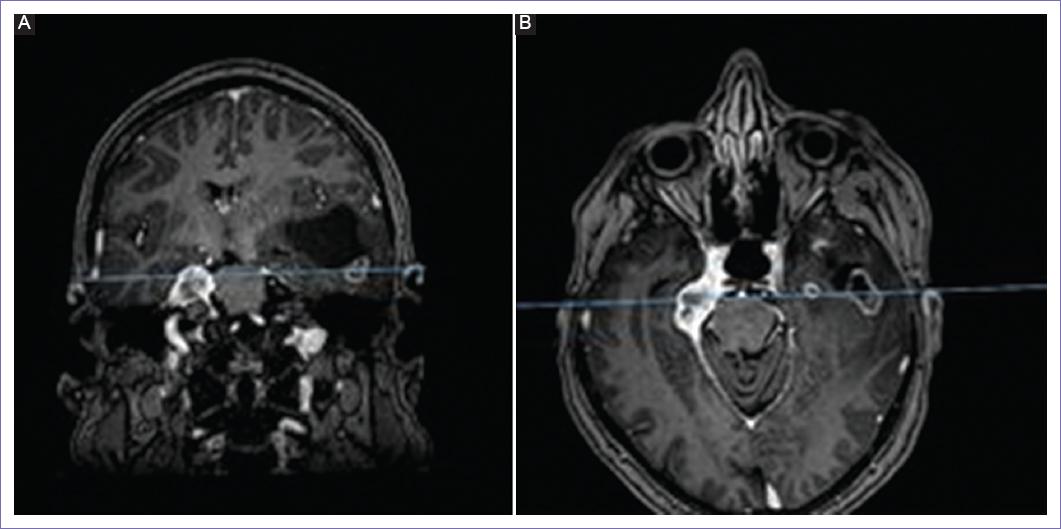

Se llega al diagnóstico por resonancia magnética, observándose tres lesiones, un meningioma tentorial derecho, una lesión glial temporal izquierda, y un cavernoma en puente Zabramski tipo 2 (Figs. 3 y 4). El electroencefalograma reporta actividad interictal en región temporal izquierdo.

Figura 3 Resonancia magnética contrastada en la cual se aprecia lesión temporal glial izquierda (A) y meningioma tentorial derecho (B).